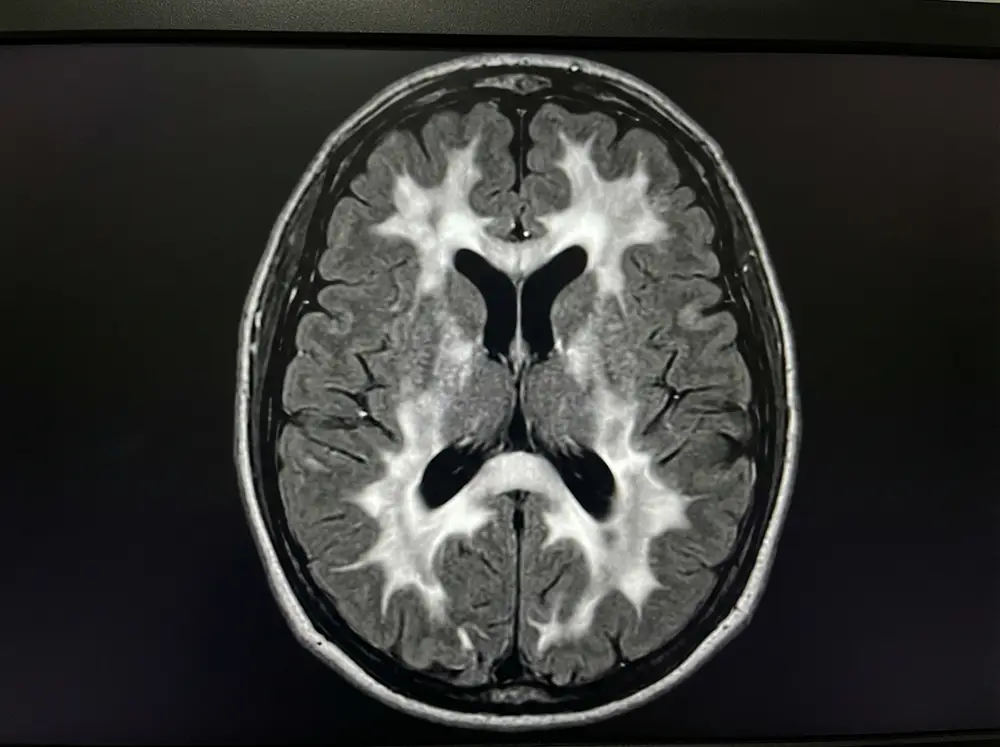

L’IRM cérébrale, examen de référence

L’IRM cérébrale est l’examen incontournable pour détecter et évaluer les anomalies de la substance blanche. En particulier, la séquence FLAIR (Fluid Attenuated Inversion Recovery) est la plus sensible pour mettre en évidence les hypersignaux FLAIR, ces zones blanches anormales qui signent une atteinte des fibres nerveuses. Le neuroradiologue analyse la taille, le nombre, la localisation et la distribution de ces lésions.

L’échelle de Fazekas : interpréter son score

Pour quantifier et classer les lésions de la substance blanche observées à l’IRM, les neuroradiologues utilisent l’échelle de Fazekas, mise au point en 1987 par le neurologue László Fazekas. C’est l’outil de référence international pour évaluer la sévérité de la leucopathie vasculaire. Elle distingue deux types de lésions — les hypersignaux périventriculaires (autour des ventricules cérébraux) et les lésions de la substance blanche profonde ou sous-corticale — et les classe en quatre grades :